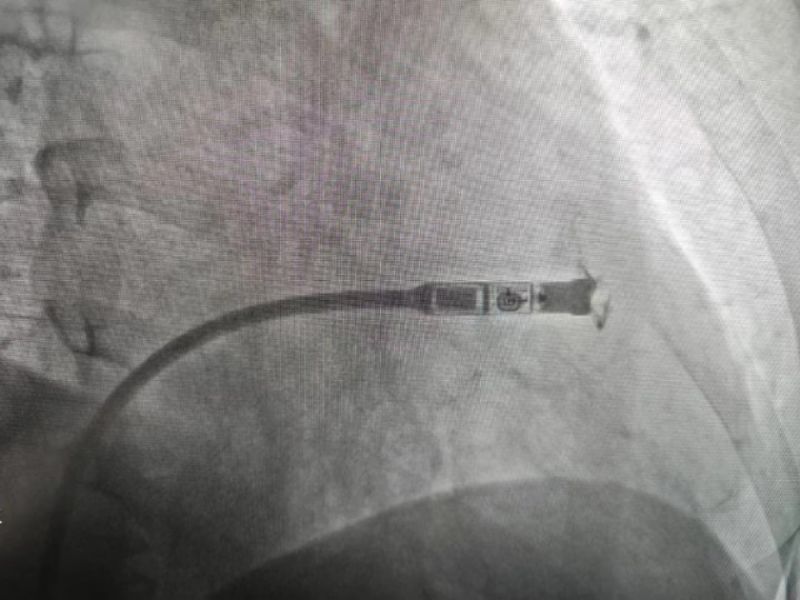

手術(shù)過程:經(jīng)過充分的術(shù)前討論,在延安大學(xué)咸陽醫(yī)院心血管病院吳棟梁院長(zhǎng)、劉雄濤副院長(zhǎng)的指導(dǎo)與支持下,李陽教授、何克強(qiáng)主治醫(yī)師、辛浩主治醫(yī)師與導(dǎo)管室介入團(tuán)隊(duì)的共同努力下,經(jīng)過超聲科、心電中心等多學(xué)科協(xié)作,成功為患者植入雙腔無導(dǎo)線永久起搏器,術(shù)后第二天患者在起搏器保障下經(jīng)藥物治療恢復(fù)正常的竇性心律。目前患者心臟情況及腦梗均恢復(fù)良好,已順利出院。

科普:Micra無導(dǎo)線起搏器號(hào)稱“世界最小起搏器”,無需植入心內(nèi)膜導(dǎo)線,也無需在胸前皮下制作囊袋放置脈沖發(fā)生器(起搏器),手術(shù)僅需局部麻醉,通過股靜脈穿刺,將起搏器經(jīng)導(dǎo)管植入心腔內(nèi),手術(shù)時(shí)間短,減少出血、血腫及感染風(fēng)險(xiǎn),術(shù)后恢復(fù)快,肢體活動(dòng)不受限,無異物感。